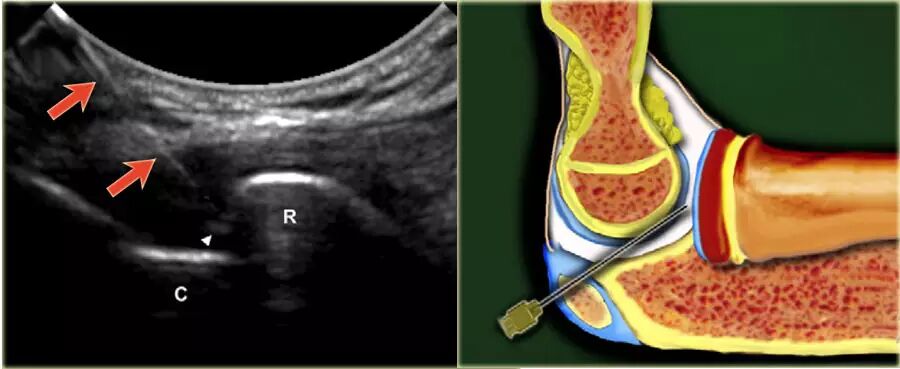

超声引导的跗骨窦的注射在右手侧与外侧入路。探头保持在冠状倾斜平面中。针沿着探头的长轴引入。

使用超声波可以容易地观察窦性骨壁。患者转向对侧,将待治疗的足以其内侧表面靠在桌面上,脚的外侧位于最上面。探头保持在关于脚的冠状平面中。

在跗骨窦被识别为跟骨的前处理和距骨颈之间的三角空间。针(箭头)的前端的锥形跗骨窦,这是由距骨(T)和跟骨(C)的边界内可以看到。